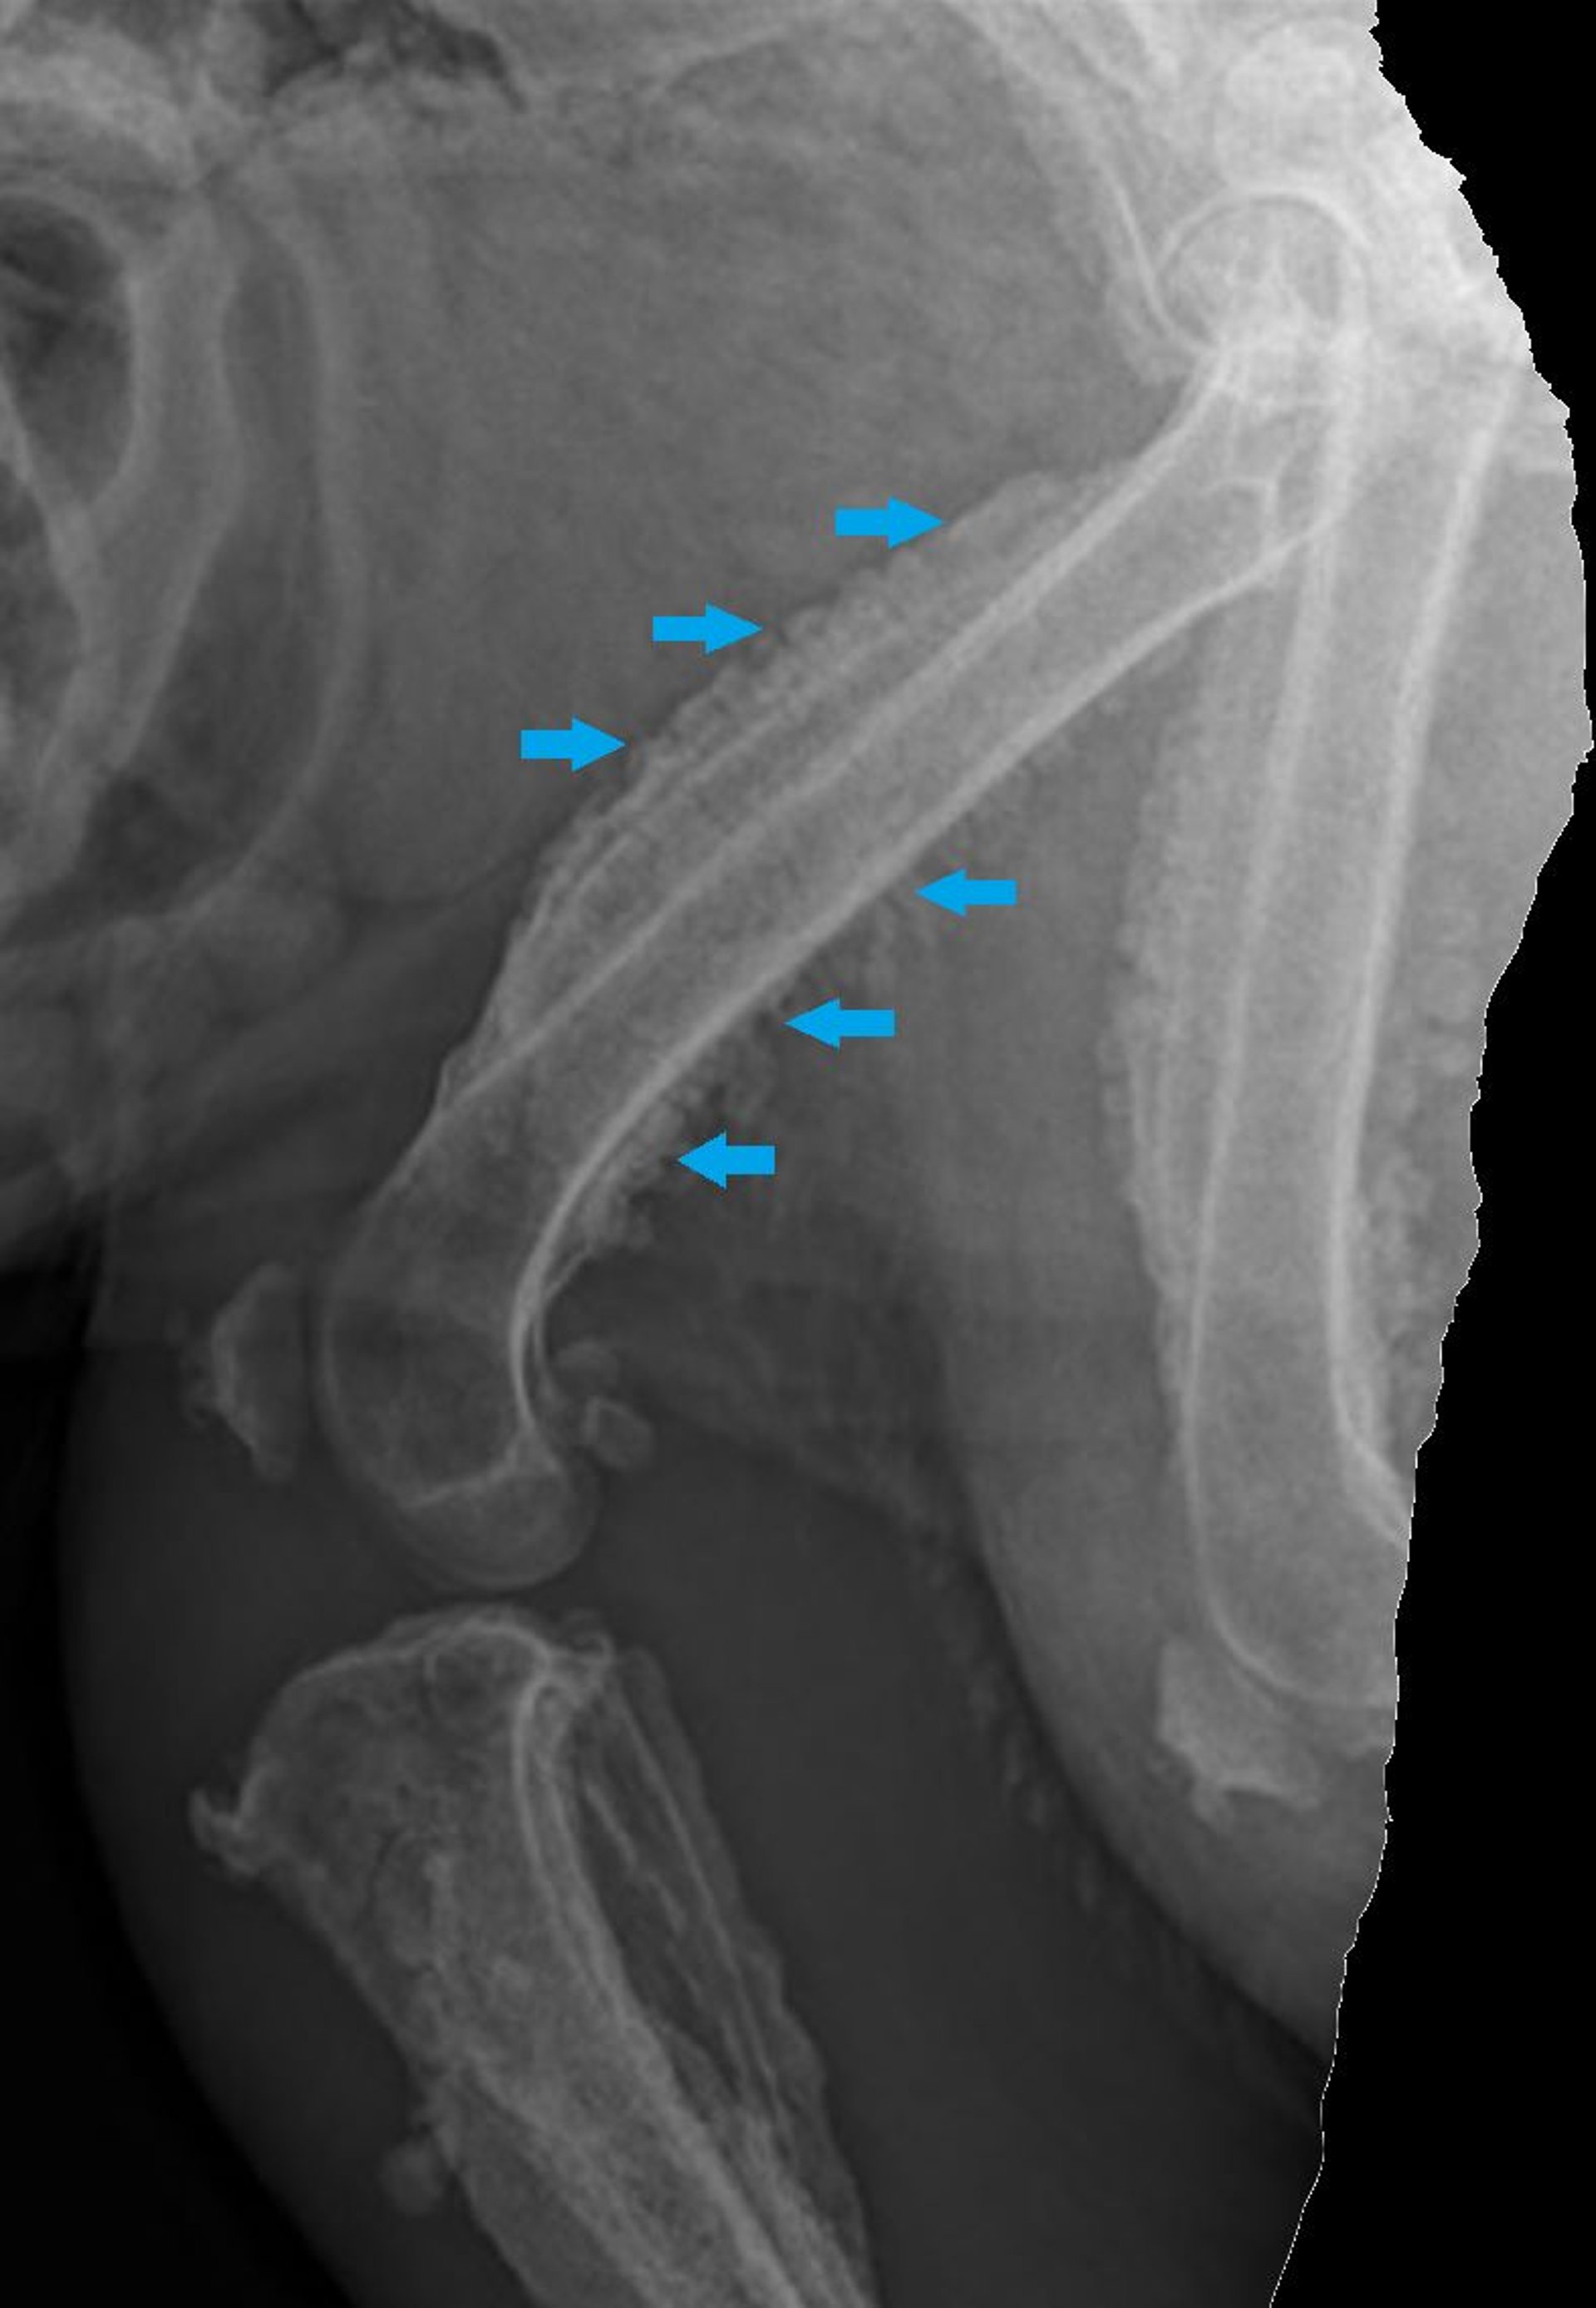

Lateral radiograph of the hindlimb of a dog with shifting leg lameness, showing an exuberant periosteal reaction (arrows) consistent with paraneoplastic hypertrophic osteopathy.

Courtesy of Dr. Brooke Britton.